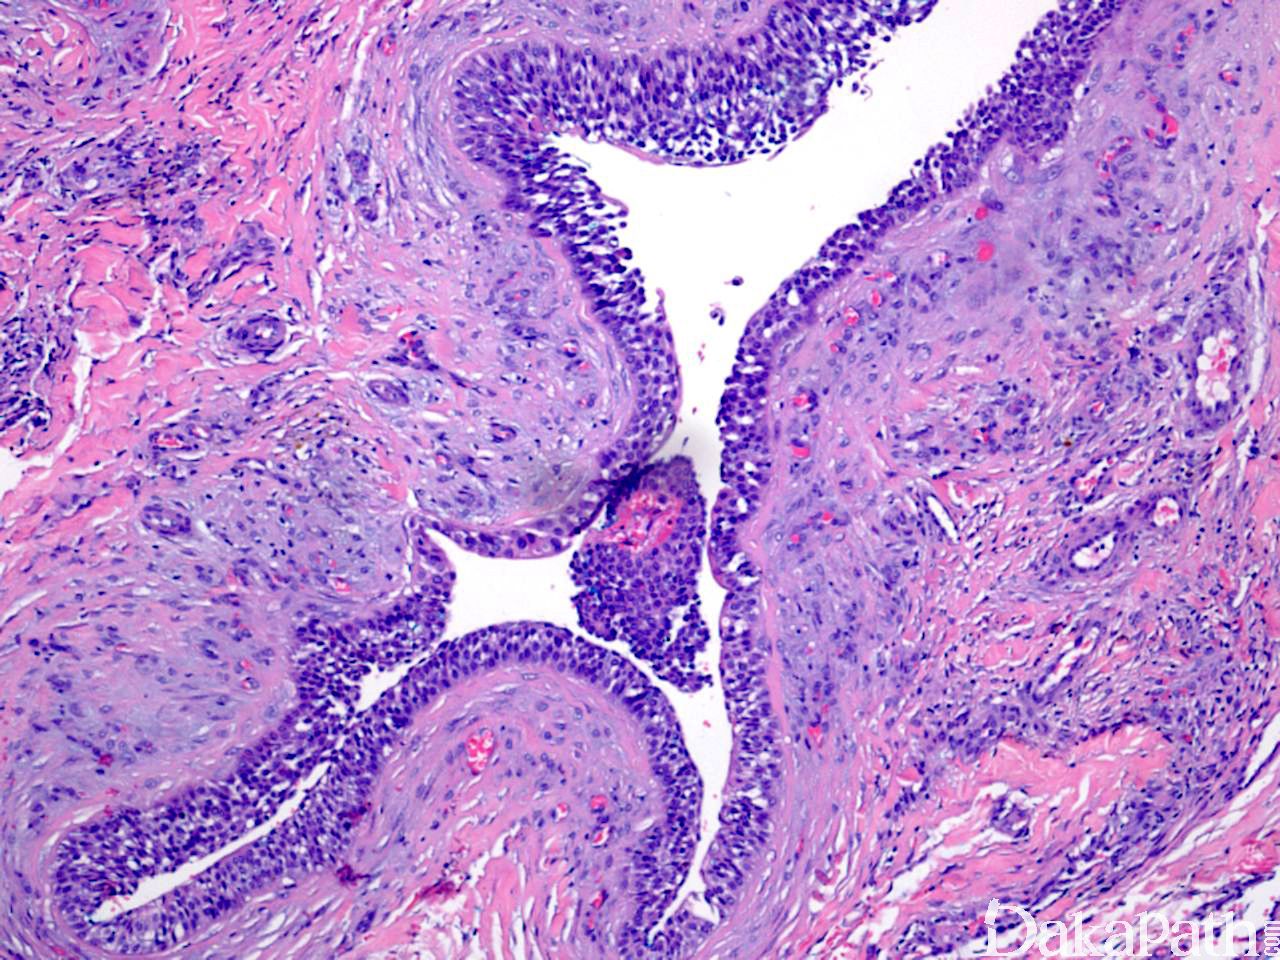

镜下见一致的嗜酸性细胞或糖原丰富透亮大汗腺样细胞增生,形成巢状或小叶状结构;

整个病变均可见到导管结构,一些导管扩张形成囊性区域,囊内充满粉染分泌物;

导管和囊性结构内衬立方形导管细胞或柱状分泌细胞,核形规则,染色质轻度增多,核分裂象少见;

某些区域可见鳞状分化,甚至角化珠形成;

间质纤维化,可伴有广泛的透明变性;